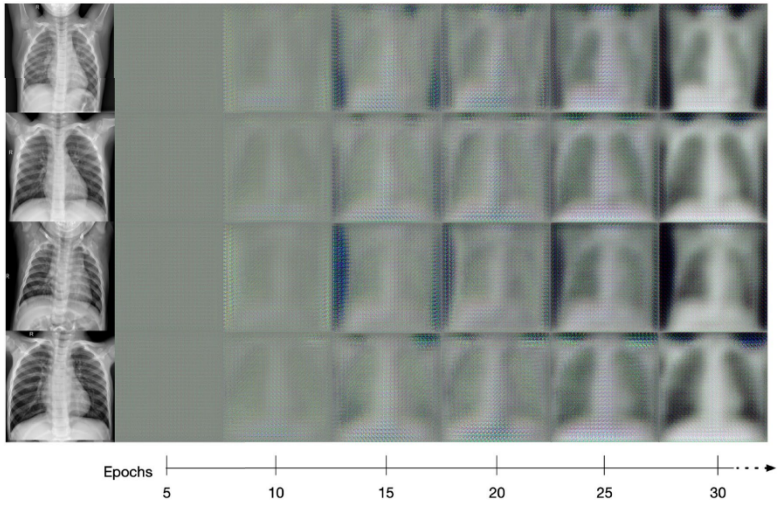

NSTDA,Neural Style Transfer as Data Augmentation,是一种将神经风格迁移作为改进 COVID-19 诊断分类的数据增强方法。这项工作显示了循环生成对抗网络的有效性,该网络主要用于神经风格迁移,增强 COVID-19 负 x 射线图像以转换为正 COVID 图像以平衡数据集并增加数据集的多样性。该方法充分表明了使用 Cycle GAN 增强图像可以提高几种不同 CNN 架构的性能。